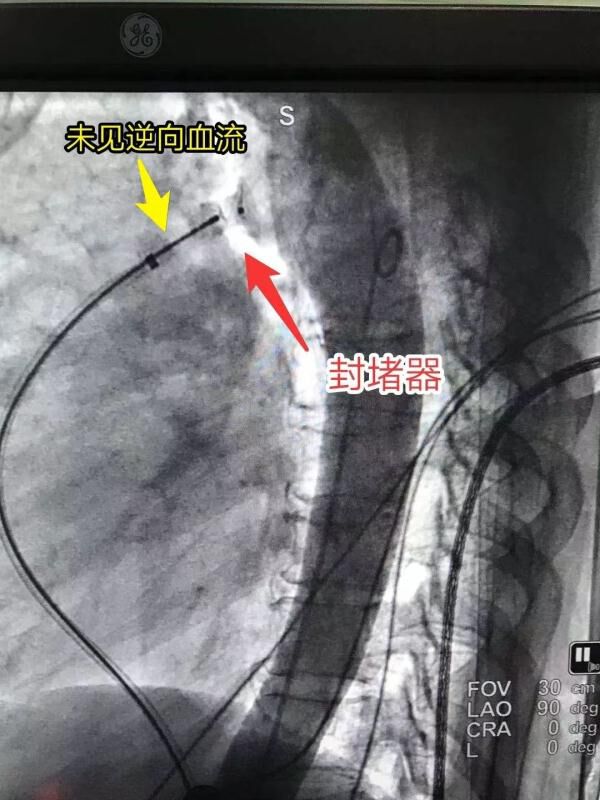

造影可见逆向血流,提示动脉导管未闭

封堵效果显著,介入封堵术取得成功

动脉导管未闭封堵术,就是将封堵器嵌入导管主动脉侧,将原本主动脉和肺动脉分叉处的闭口“堵上”,使心脏恢复正常的血流动力学。

完成检查后,就到了封堵治疗的环节。医生需要将导丝从肺动脉一侧通过动脉导管送到主动脉一侧。这一步是手术的关键步骤之一,也是难点之一。导丝通过后,再输送封堵器,将动脉导管的闭口堵上,使心脏恢复正常的血流动力学。